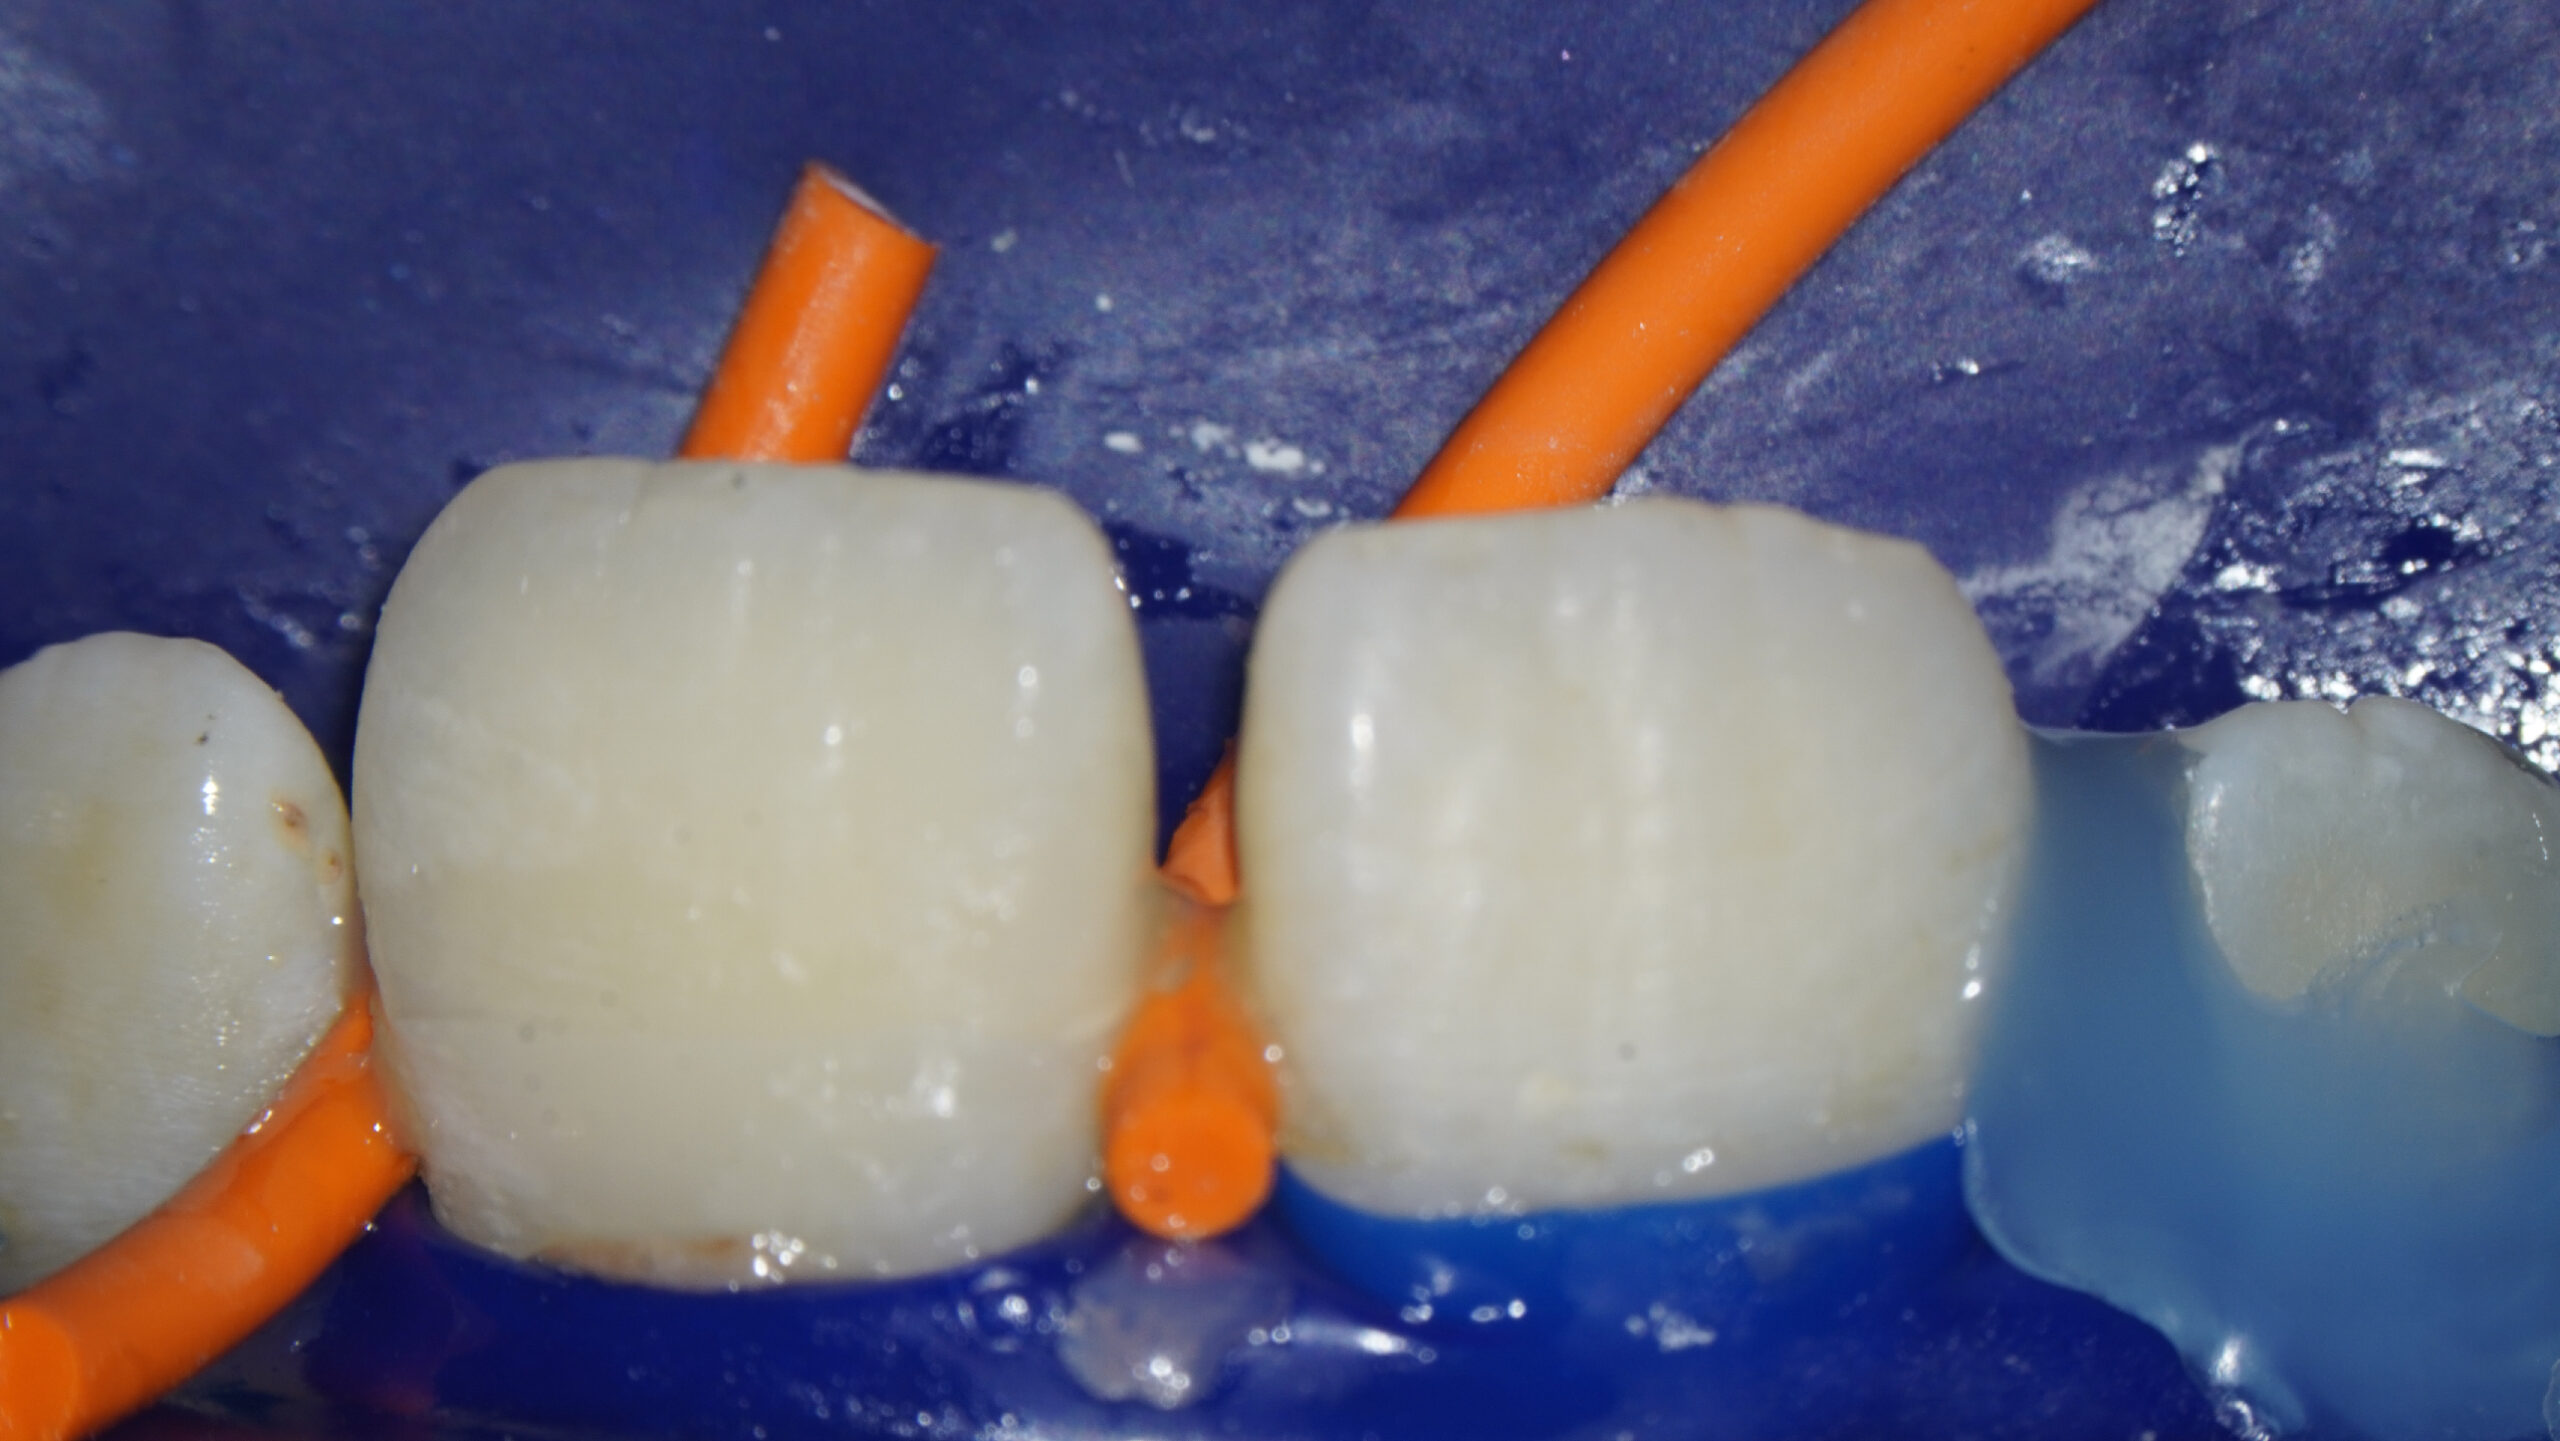

2.1 fractura coronal